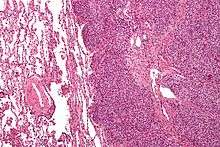

The definitive diagnosis is based on histomorphologic findings, immunohistochemistry and molecular pathology.

Ewing's sarcoma is a small-blue-round-cell tumor that typically has a clear cytoplasm on H&E staining, due to glycogen. The presence of the glycogen can be demonstrated with positive PAS staining and negative PAS diastase staining. The characteristic immunostain is CD99, which diffusely marks the cell membrane. Morphologic and immunohistochemical findings are corroborated with an associated chromosomal translocation, of which several occur. The most common translocation, present in about 90% of Ewing sarcoma cases, is t(11;22)(q24;q12),[12][13] which generates an aberrant transcription factor through fusion of the EWSR1 gene with the FLI1 gene.[14]

The pathologic differential diagnosis is the grouping of small-blue-round-cell tumors, which includes lymphoma, alveolar rhabdomyosarcoma, and desmoplastic small round cell tumor, among others.